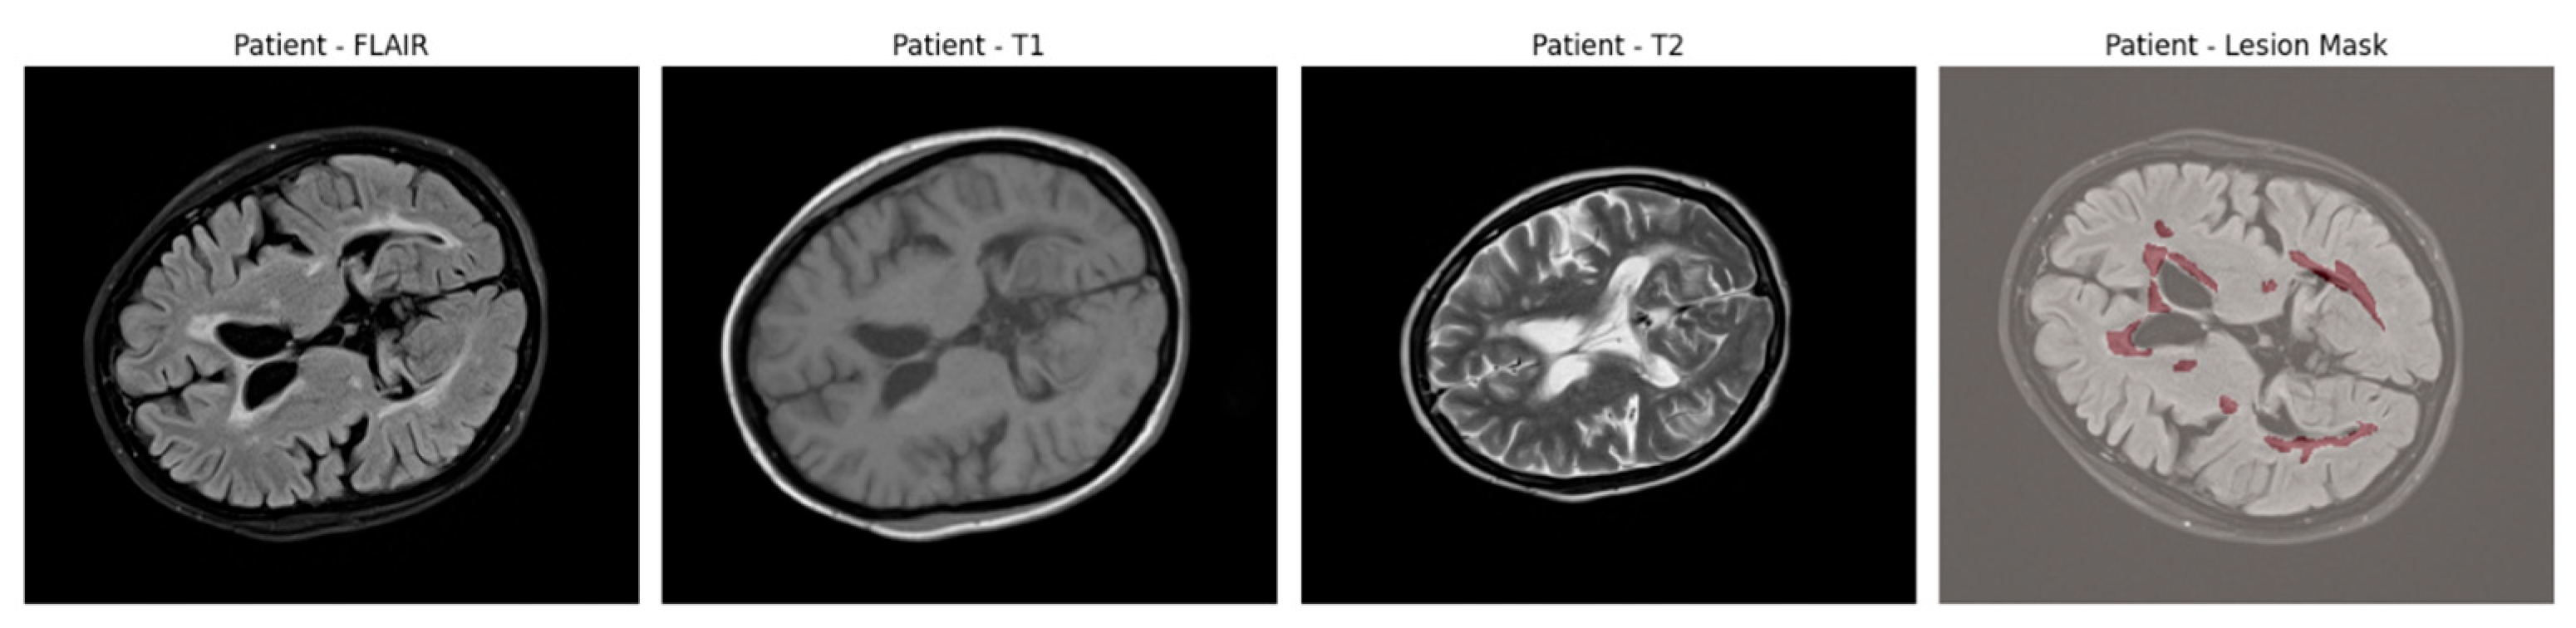

An example of axial slices from a representative patient is shown in Figure 1, showing the T1, T2, and FLAIR modalities alongside the corresponding lesion mask overlaid on the FLAIR scan. This highlights the multi-modal nature of the dataset and the spatial distribution of lesions across white matter regions.

Figure 1. Axial brain slices from a representative MS patient showing the T1-weighted, T2-weighted, and FLAIR MRI sequences. The final panel overlays the expert-annotated lesion segmentation (in red) on the FLAIR image.